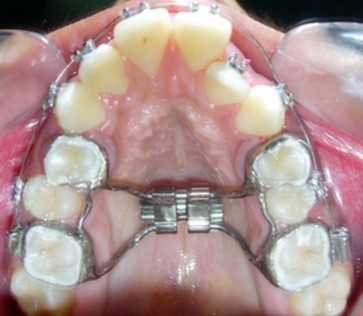

The main treatment objective was to improve the phonation, lip competence, smile esthetics and soft tissue profile. The initial phase of treatment was initiated with a banded rapid palatal expansion appliance to correct the bilateral maxillary posterior crossbite. (Figure 4). Subsequent to correction of the same, maxillary and mandibular first premolars were extracted and the orthodontic phase was commenced to correct the severe crowding of the maxillary and mandibular dental arch.

Figure 4.Banded Rapid Palatal Appliance

Banded Rapid Palatal Appliance

Though bonded RME could have been used, we however, preferred to use banded RME as it is more hygienic and easy to maintain with good patient co-operation.

Treatment Progress

The mandibular first premolars were first extracted to commence treatment of the mandibular arch simultaneously with expansion of the constricted maxilla. Preadjusted edgewise brackets (Roth prescription, 0.022 x 0.028-inch slot) were initially bonded to the maxillary and mandibular teeth. Banded Hyrax (Hygienic rapid palatal expander) was cemented to the maxillary first premolars and molars. (Figure 5). The patient was advised to activate the appliance a quarter turn once or twice a day to achieve adequate expansion consistently. Subsequent to over-expansion of the maxilla the Hyrax was inactivated with a ligature tie tied into the screw holes and was retained in situ for a period of 6 months, after which the maxillary first premolars were extracted and the maxillary arch treatment was commenced.

Figure 5.Rapid palatal expansion appliance in situ

Rapid palatal expansion appliance in situ